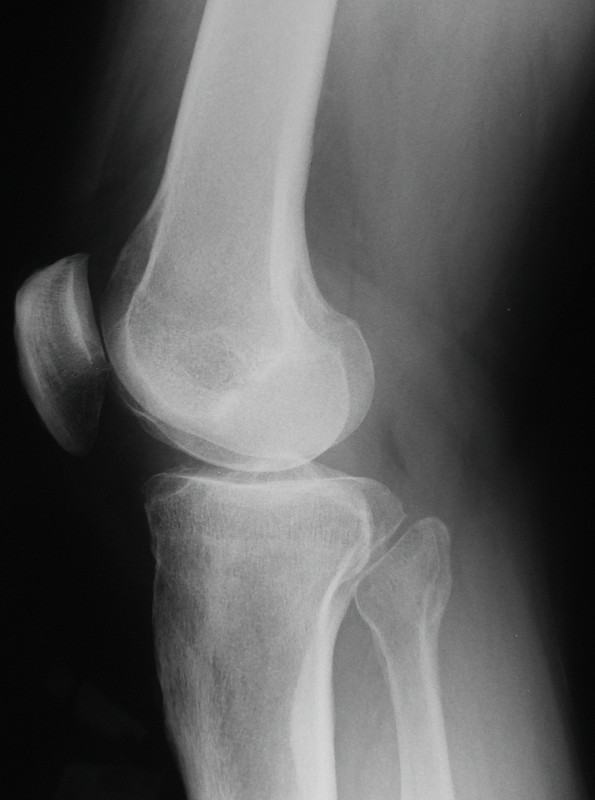

髋部x线图像详情

胶片x射线扫描人详情